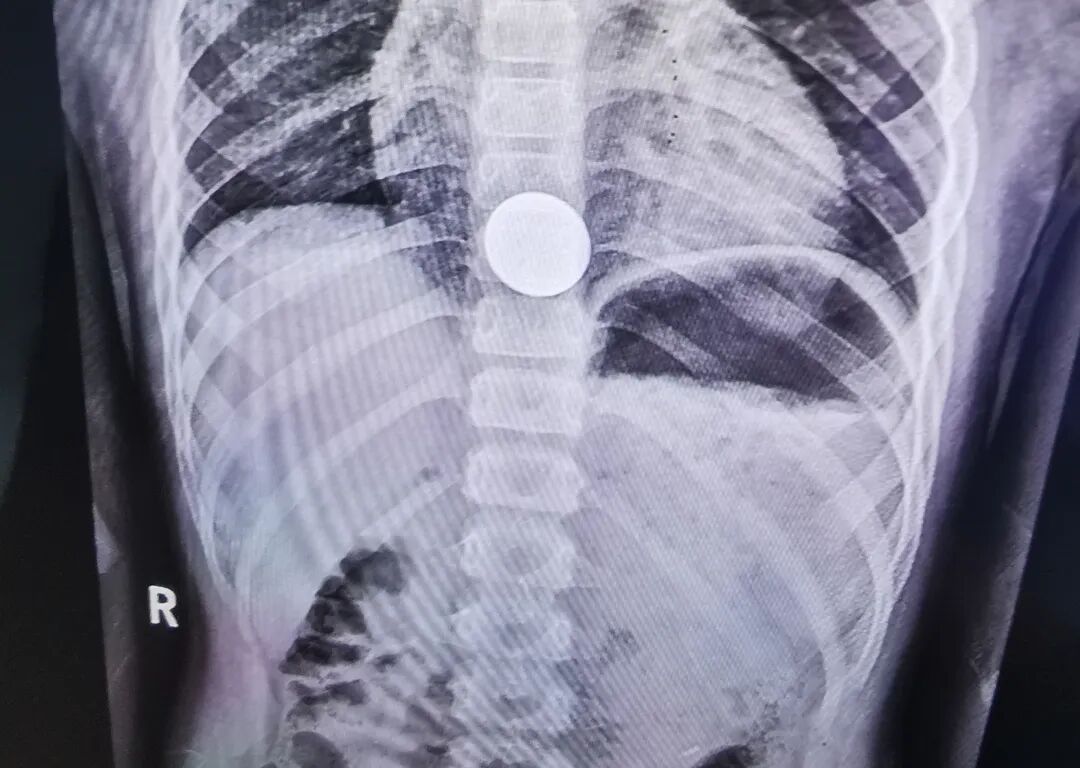

吓人,5岁孩子不小心误吞1元硬币

5月29日下午5点半,一对家长抱着孩子急匆匆奔入新泰市中医医院综合楼三楼小儿外科门诊,小儿外科坐诊专家询问得知患者来自新泰羊流,该五岁孩子在玩硬币时,不小心把一枚1元硬币从嘴里吞下,在当地卫生院拍胸片后建议到上级医院诊疗。

当妈妈抱着小患者出现在李迎吉主任的面前时,孩子用手捂着自己的胸口下方,一直喊着:“妈妈,疼!妈妈,疼!……”看过孩子妈妈手机里拍存的胸部片子,发现硬币卡在食管下段、膈肌上水平。李迎吉介绍,因为孩子年龄小,贲门狭窄,硬币卡在食管下端下不去,在此部位较危急,食管痉挛导致孩子异常疼痛,时间长了还会引起出血、溃疡甚至穿孔。